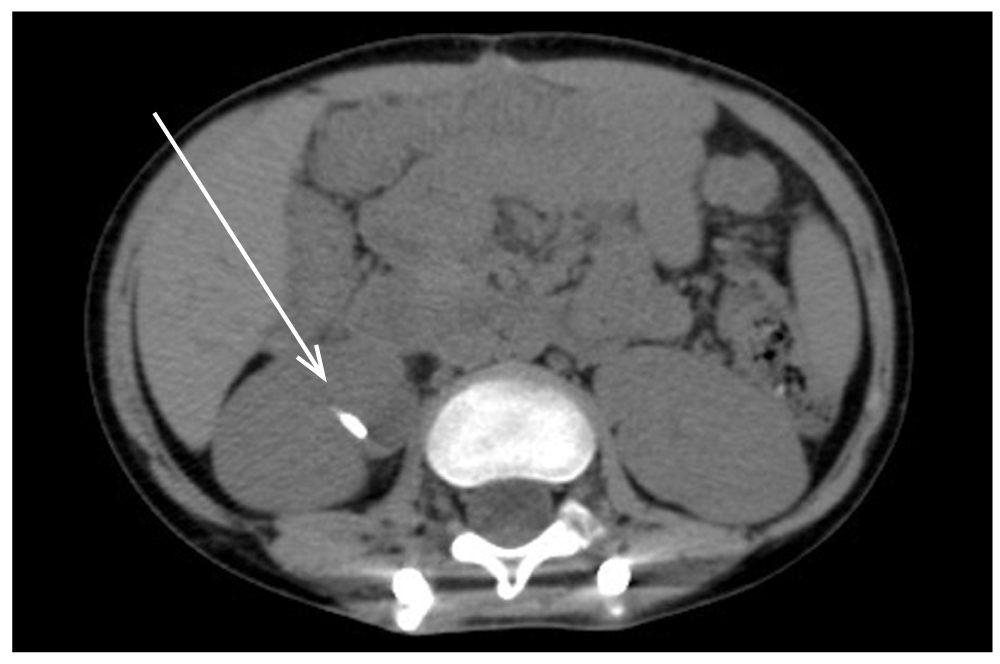

На реабилитацию с тромбозами нижних конечностей в стадии реканализации поступили 12 (19,7%) детей этой группы, у 5 (8,2%) из них была выявлена мочекаменная болезнь (рис. 2). У 3 (14,3%) детей II группы при поступлении на реабилитацию были выявлены гетеротопические оссификации (рис. 3).

Рис. 2. Компьютерная томография: мочекаменная болезнь, картина высокоплотного конкремента в лоханке правой почки (стрелка). / Fig. 2. Computed tomography: picture of urolithiasis, a high-density calculus in the pelvis of the right kidney (arrow).